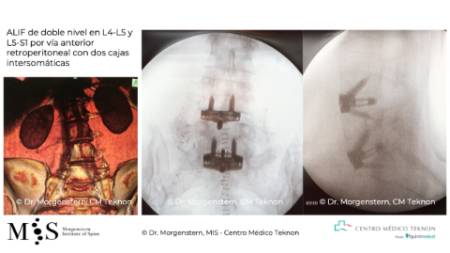

At the Morgenstern Institute of Spine we use endoscopic, percutaneous and minimally invasive surgical techniques that allow us to bypass previously operated areas and hence, avoid the patient’s internal scar tissue, lowering the risks of infection and an accidental injury. Surgical approaches like i.e. the anterior approach or endoscopic fusion surgery allow us to access the spine from the side or the front (through the belly) and circumvent previously operated tissue. Hence, patient recovery is much faster than with traditional approaches.